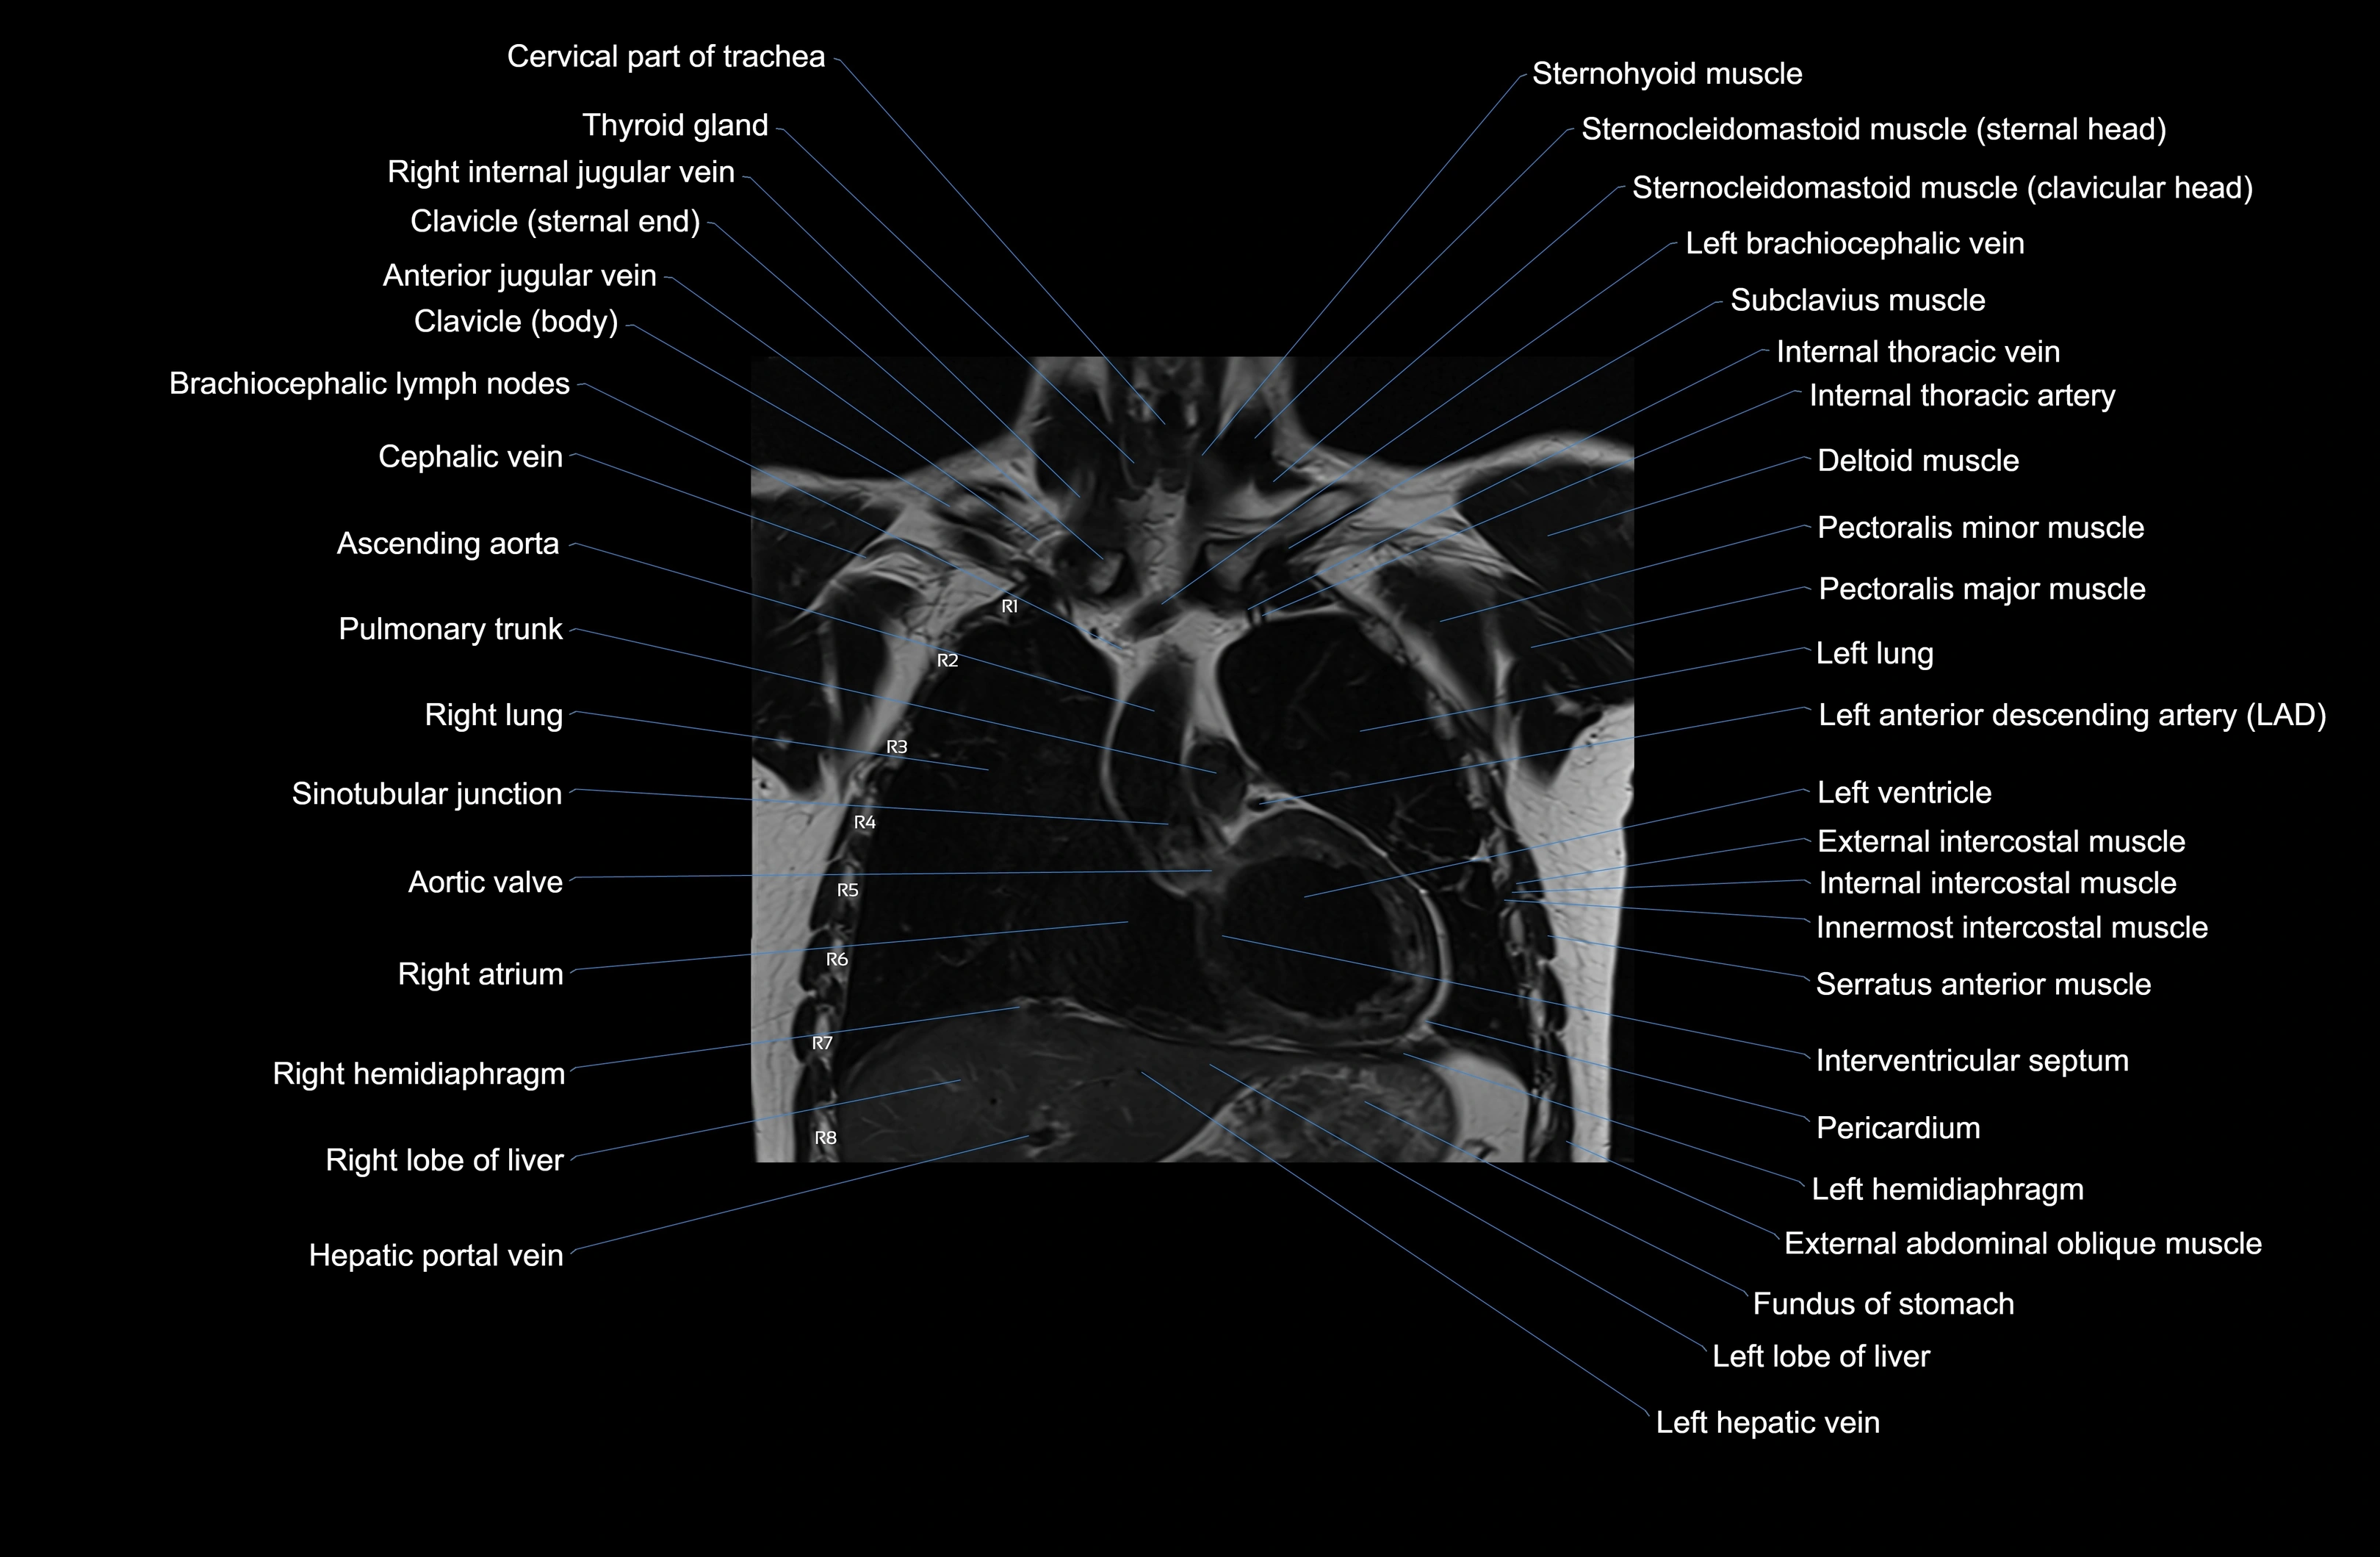

- Ascending aorta

- Cephalic vein

- Internal thoracic artery

- Internal thoracic veins

- Interventricular Septum

- Left anterior descending artery (LAD)

- Left ventricle

- Pericardium

- Pulmonary trunk

- Right atrium

- Right hemidiaphragm

- Right lobe of liver

- Right ventricle

- Serratus anterior muscle

- Sternocleidomastoid muscle

- Sternohyoid muscle

- Subclavius muscle

- Superior vena cava

- Thyroid gland

- Trachea